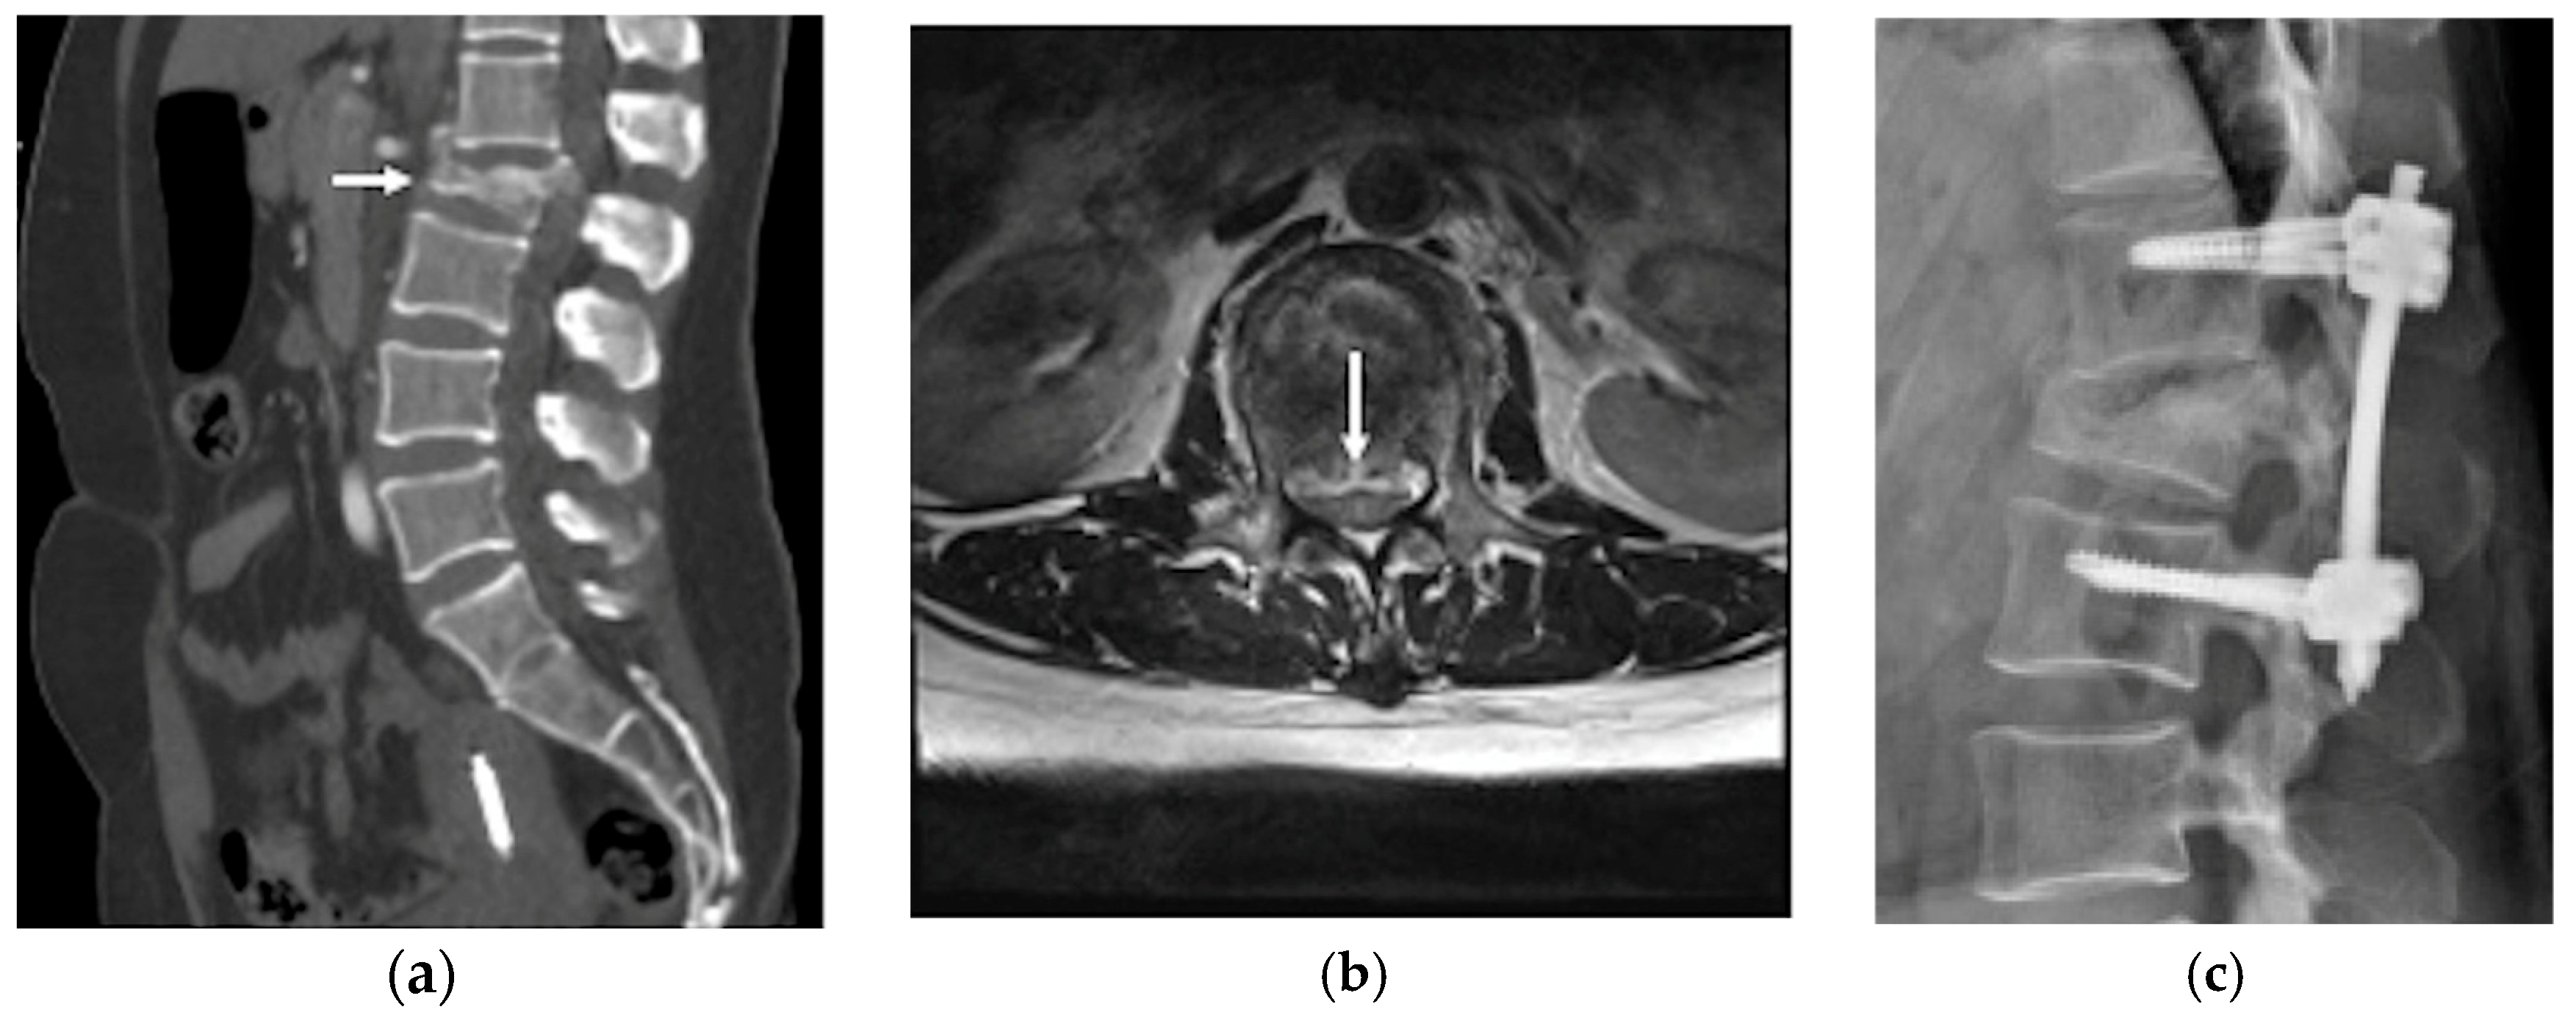

A non-contrast brain computed tomography (CT) scan revealed diffuse subarachnoid hemorrhage (SAH) with a thickness exceeding 1 mm within the basal cistern, predominantly along the left side ambient cistern (Figure 1a). Subsequent CT angiography (CTA) was performed to investigate the etiology of the SAH and demonstrated an irregular vessel contour in the left PCA P2 segment, with a focal arterial pouch consistent with a dissecting aneurysm with a saccular rupture component (Figure 1b). Evaluation of the lumbar spine using CT (Figure 2a) and axial T2-weighted magnetic resonance imaging (MRI) (Figure 2b) revealed an L2 burst fracture with significant spinal canal compromise, resulting in approximately 65% dural sac stenosis. Digital subtraction catheter angiography (DSA) with 3D rotational angiographic acquisition was performed using the Siemens Artis Q angiography system with PURE technology (Siemens Healthineers, Forchheim, Germany). Image reconstruction and aneurysm morphometric quantitative measurements were performed on the Siemens syngo X-Workplace using the syngo 3D Angio (Dyna3D) module. The DSA identified an approximately 5 mm long fusiform dilation along the anterior portion of the left PCA P2 segment (Figure 3a, D1), accompanied by an inferiorly projecting saccular pouch measuring 2.5 mm in diameter (Figure 3a, D2). These findings were diagnostic of a ruptured dissecting aneurysm with a superimposed saccular aneurysm sac (Figure 3a). All cerebrovascular imaging examinations was performed by neuroradiologist Dr. Wu Ming-Ji. A second neuroradiologist Dr. Shen Chao-Yu independently reviewed the images and confirmed the morphometric measurements.

Figure 2.

(a) Lumbar spine CT scan identified burst fractures in the L2 vertebral with spinal canal compromise (white arrow); (b) lumbar spinal magnetic resonance imaging (MRI) T2 weighted image axial view confirmed an L2 level severe spinal canal compromise, resulting in approximately 65% dural sac stenosis (white arrow); (c) lumbar spine lateral view showed percutaneous transpedicle screw fixation from L1 to L3.